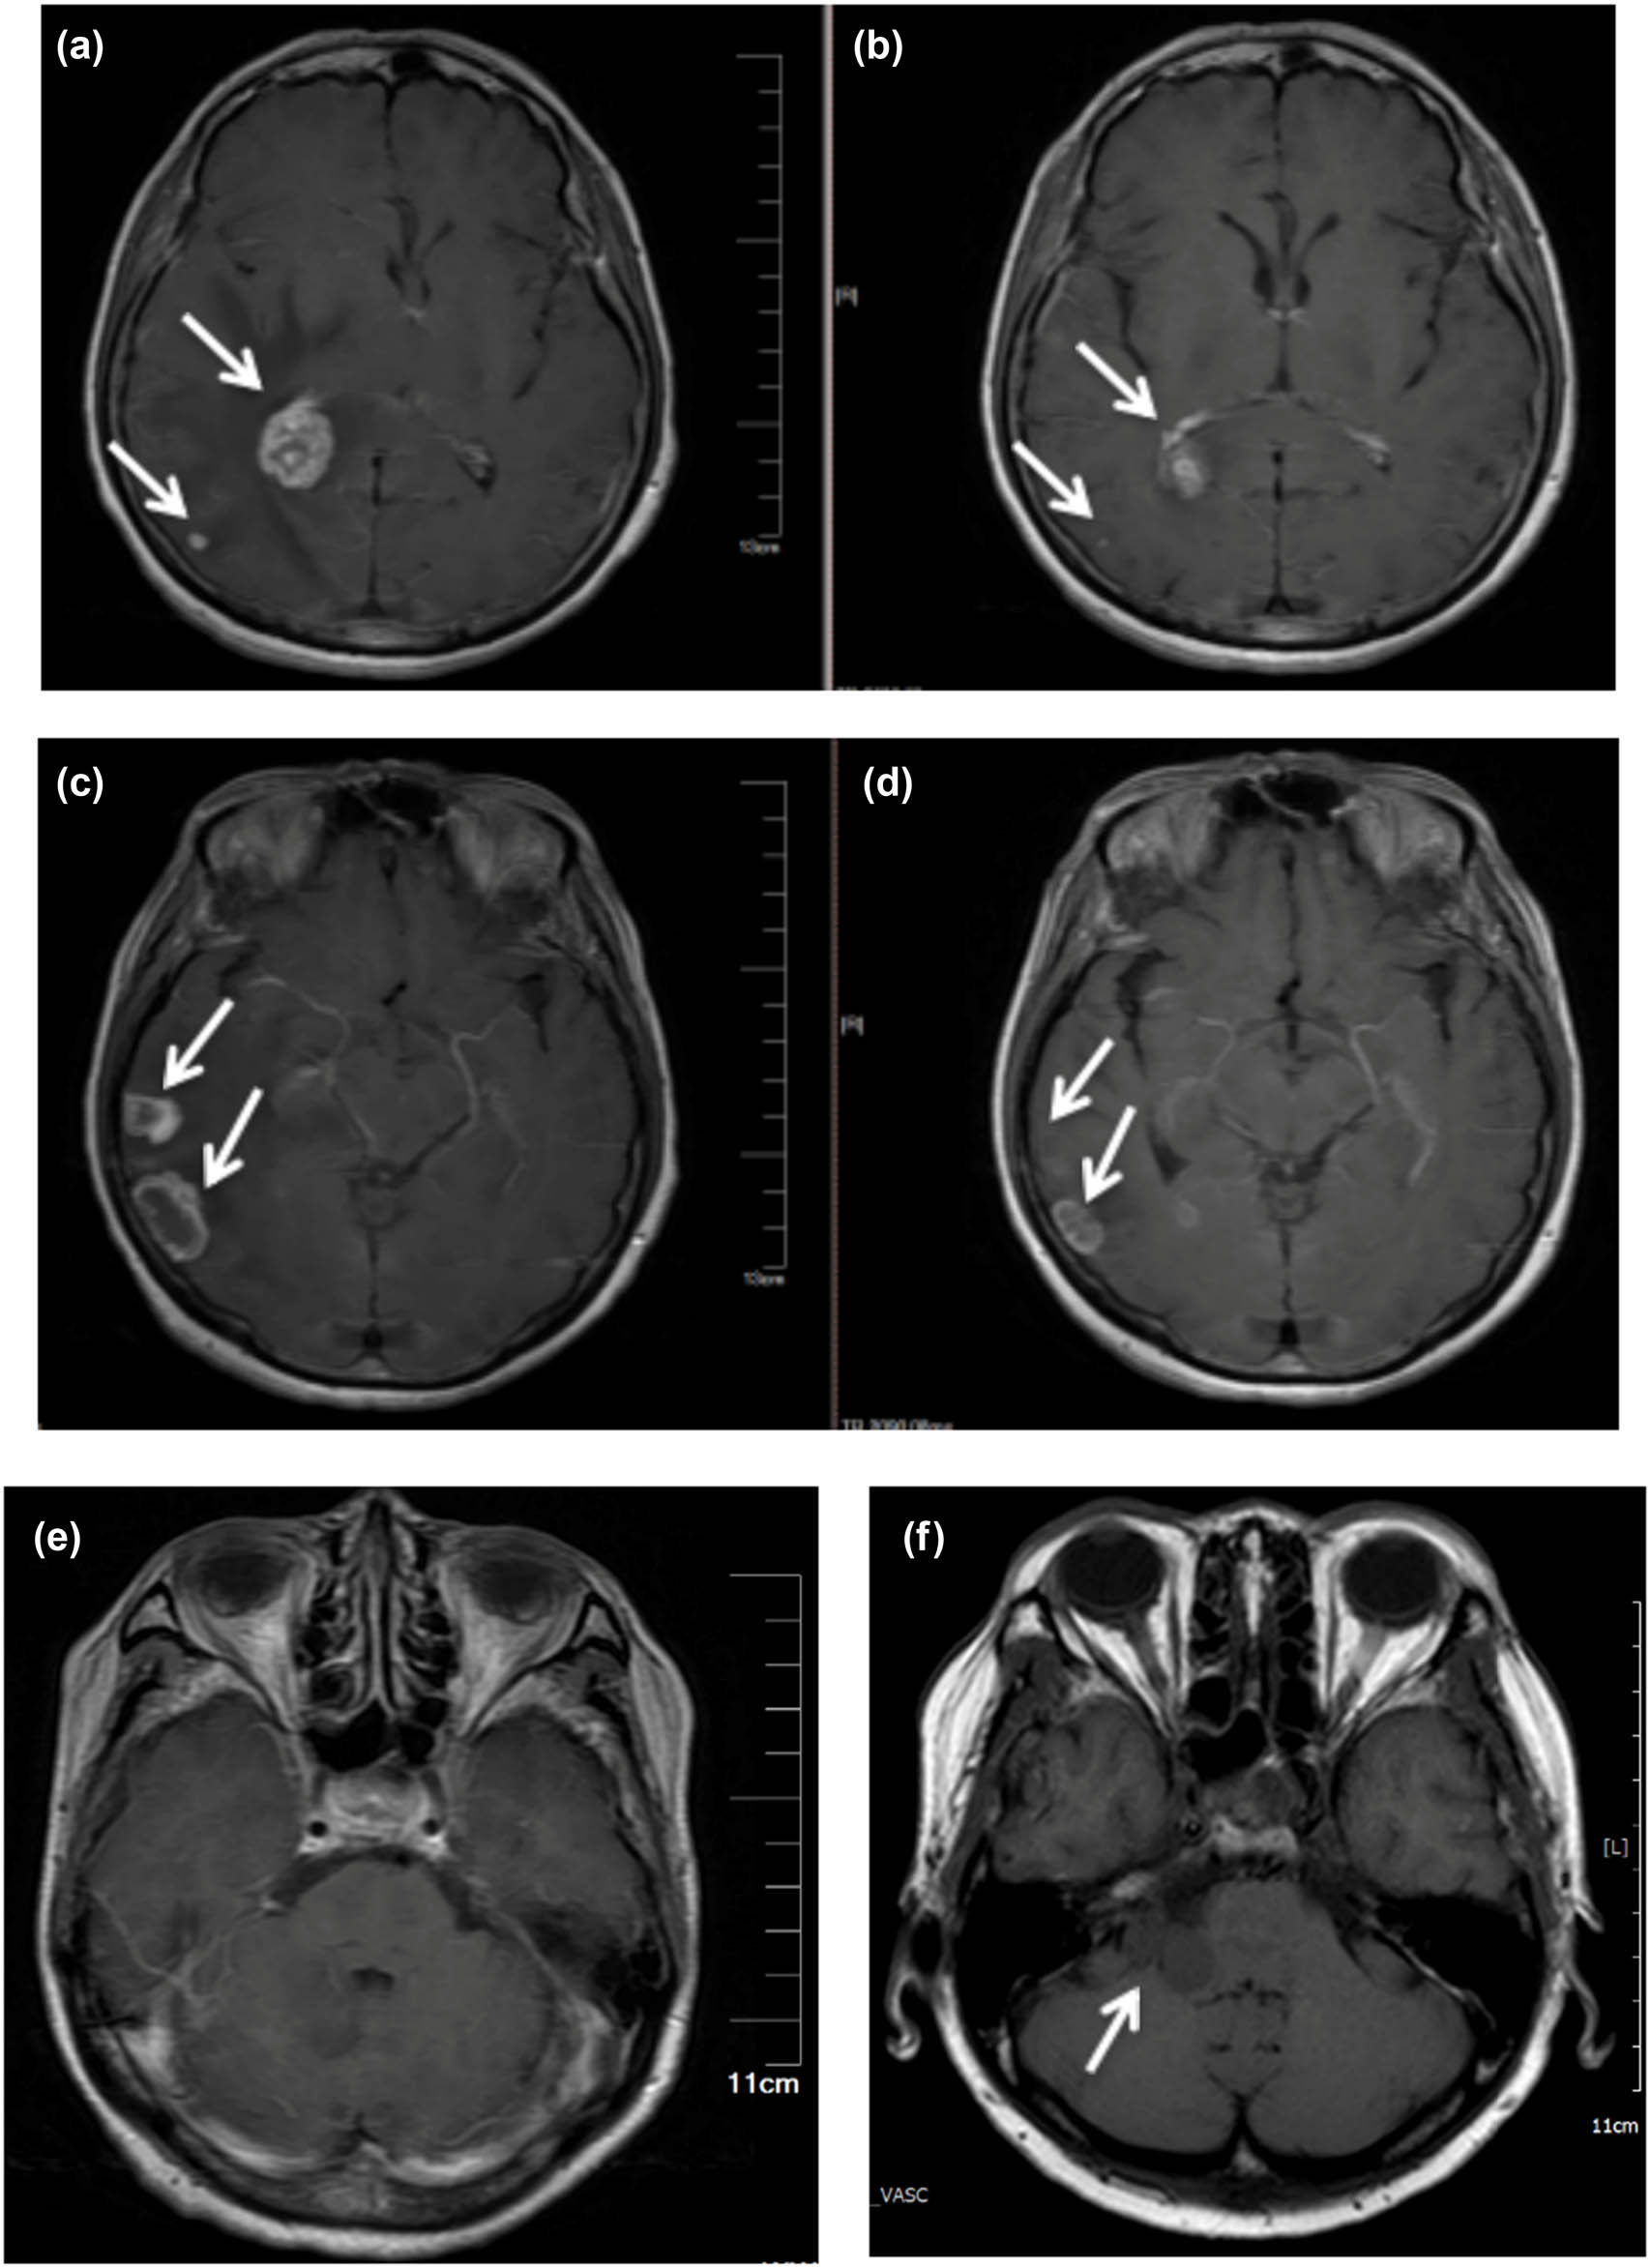

The 63-year-old female never-smoker was admitted to our department for the first time on December 23, 2015, due to cough and dyspnea for over 20 days. Her chest computed tomography (CT) showed space-occupying lesions in the right hilum and enlarged lymph nodes in the mediastinum, atelectasis of the right lung, massive pleural effusion in the right side, and multiple nodules in both lungs (Figure 1a). Magnetic resonance imaging (MRI) showed gadolinium-enhanced multiple abnormal intensification foci in the brain which were considered to be multiple metastatic tumors (Figure 2a, c, and e). The serum concentration of the carcinoembryonic antigen (CEA) was 18.75 ng/mL. Right thoracic closed drainage and pleural biopsy were performed, resulting in a total of 1,500 mL yellow pleural fluid drained out (Figure 1b) and a pleural fluid CEA of 17.55 ng/mL.

Multiple BMs revealed by MRI. (a and b), (c and d), and (e and f) are image comparison of the same part, respectively. (a), (c), and (e) At initial visit, (b) and (d) after targeted therapy of gefitinib, and (f) a new metastasis was found in the right cerebellar hemisphere.

The patient received gefitinib and intermittent zoledronic acid for bone metastases until 20 months, and then MRI showed that BMs which had disappeared and shrunk (Figure 2b and d) after gefitinib were progressing again. The cancer lesions in lungs of the patient were significantly reduced (Figure 1c) after gefitinib and did not progress during the treatment period. Systemic bone imaging showed that the metabolic activity of hypermetabolic lesions in the middle part of the left femur was significantly decreased after gefitinib treatment (Figure 4b) and the patient had never been affected by lower limb discomfort.

The patient received osimertinib for 38 months which was recommended after T790M acquisition confirmed by liquid biopsy after brain MRI showed progression of the disease on August 7, 2020 (Figure 2f).

Until September 8, 2020, the patient developed unilateral facial paralysis, and MRI examination showed a new metastasis in the brain.